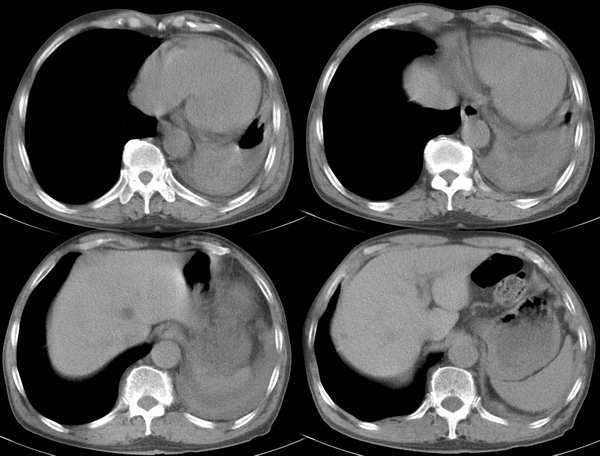

m67y外院ct诊断肺ca,现来我科复查ct

左肺下叶支气管狭窄局部见肿块影左肺下叶不张,肺癌应该没问题吧

典型中央型肺ca

左主支气管变窄,左下叶部分不张,考虑肺癌可能性大

考虑左下肺中央型肺癌并肺不张,建议支气管镜检查。

主-肺动脉窗似有大的淋巴结,肝也像有多发低密度灶。看不太清,是不是转移?

左中央型肺癌并左下叶肺不张,建议纤支镜检查.

左下肺中央肺ca并下肺不张

[emb6]大家的意见。注意肝脏。